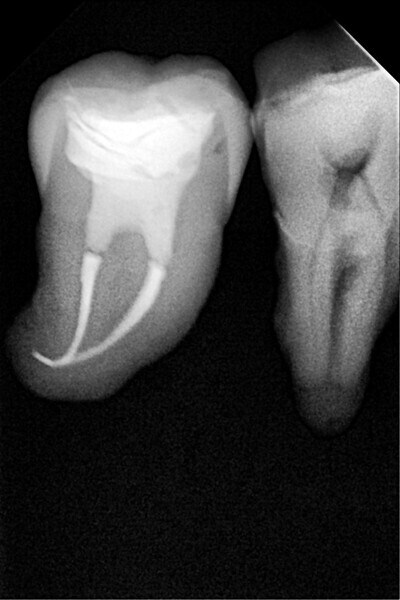

1. functional and aesthetic reconstruction of a maxillary anterior tooth using fibre-reinforced flexible micro-posts after endodontic treatment (Figs. 3–20);

Example 1—showing functional and aesthetic reconstruction of a maxillary anterior tooth using fibre-reinforced flexible micro-posts after endodontic treatment.